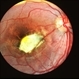

- central disciform scar

- Fundus photograph and OCT scan of an 86-year-old man with long-standing type I diabetic proliferative retinopathy.